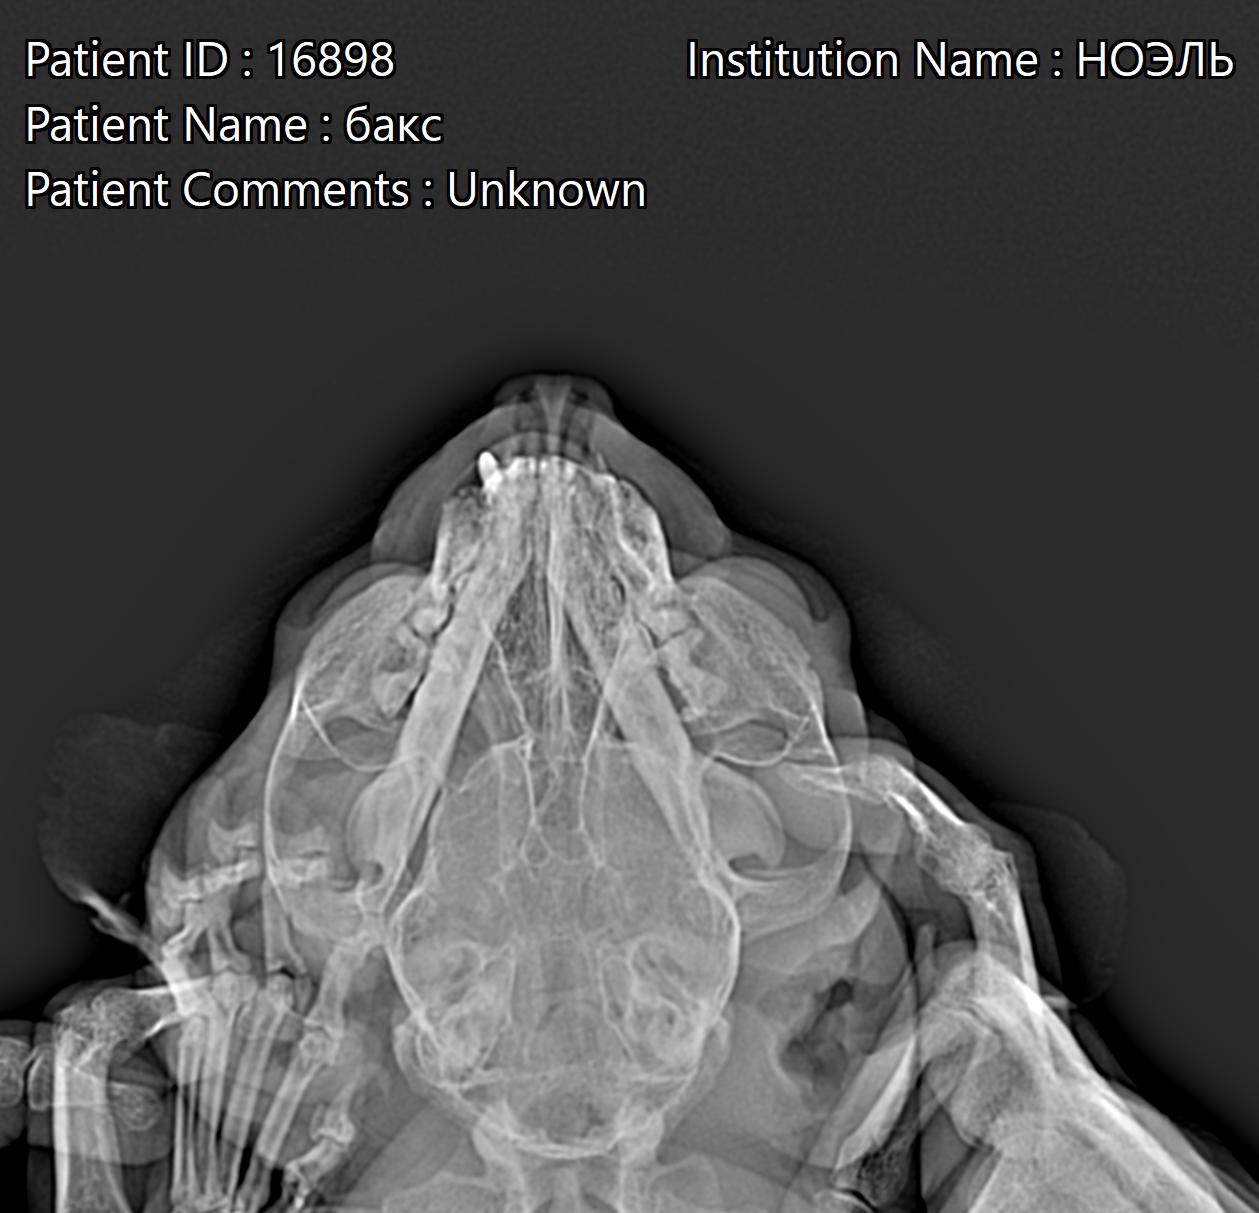

Прилагаю рентген. Снимок был сделан ДО приема Марфлоксина.

Здравствуйте. По описанию и рентгену ситуация действительно может быть связана с осложнением после удаления зубов и формированием свища или остеомиелита верхней челюсти. Симптомы (кровь из носа, слезотечение, лёгкая асимметрия мордочки) указывают на возможное вовлечение околоносовых пазух и носослёзного канала, что нередко связано именно с удалением клыков.

- важно сделать контрольный снимок после лечения или КТ головы, чтобы исключить свищ или воспаление пазух

Сейчас выбранная схема в целом оправдана, но если после курса клиндамицина симптомы (слезотечение, асимметрия, выделения крови) сохранятся тогда стоит настаивать на дополнительной диагностике (КТ/рентген пазух, бакпосев).

Здравствуйте. Ситуация действительно непростая т.к кровь из носа и слезотечение после удаления клыков могут быть признаками свища между ротовой полостью и пазухой или воспаления пазух, что нередко осложняет заживление. Назначенные антибиотики и НПВС могут временно снимать воспаление, но если симптомы повторяются, стоит проверить именно состояние верхнечелюстных пазух и провести КТ головы или прицельный рентген. Лечение в таком случае может потребовать не только антибиотиков, но и хирургической коррекции свища.